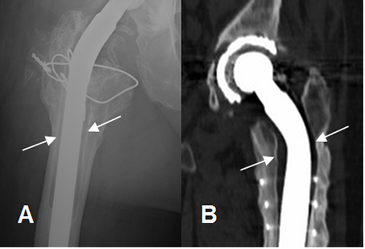

Fig 119. Aflojamiento.

A: Rx AP. Aflojamiento de la prótesis, con un espacio mayor de 2 mm.

B: TAC reconstrucción coronal. Aflojamiento de la prótesis.